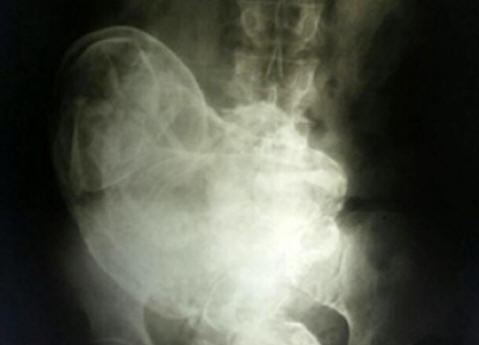

Nell’utero di una donna brasiliana di 84 anni ha scoperto un pietrificato feto di 44 anni. Questo è successo quando è stato insopportabile donna dolore addominale consultato un medico che l’ha fatta X-ray. Nella foto hanno visto un embrione pietrificato. Questo fenomeno ricevuto in uso medico il nome lithopedion. Litopedione – un feto uterino pietrificato che è morto nell’utero o nell’addome cavità, che ha subito poi calcificazione. È raro un fenomeno che si verifica principalmente quando il feto muore durante gravidanza ectopica. Dal momento che non c’è naturale modo per sbarazzarsi di un tale feto, il corpo lo espone calcificazioni per prevenire il danneggiamento del tessuto fetale in decomposizione il corpo del corriere. I dottori che hanno esaminato la donna hanno concluso che il feto è morto alla 28a settimana di gravidanza. Tuttavia dalla chirurgia il paziente ha rifiutato di rimuoverlo. Caso marocchino Questo fenomeno è molto raro, quindi i casi in cui si verificano sono di solito registrato dagli storici. Questo è descritto nel 2012. Un residente di un piccolo villaggio situato nelle vicinanze di Casablanca, Marocco, madre di tre figli Zahra Abutalib per l’ultima volta rimase incinta all’età di 26 anni. Nove mesi di gestazione il feto è passato senza complicazioni. Tuttavia, in ospedale divenne una testimone la morte di una coinquilina dell’ospedale, una giovane madre che è morto sul tavolo operatorio a seguito di taglio cesareo. non è riuscito a salvare suo figlio. Temo che un tale destino possa aspettiamo che lei, Zahra impressionabile, che raccoglie cose, sia scappata ospedali, decidendo di partorire a casa. Nei prossimi giorni ha sofferto terribilmente di dolori alla nascita, tuttavia tanto atteso il bambino non è mai venuto al mondo. Si fermò presto del tutto muoversi nell’utero e la donna decise che il bambino “si addormentò”. Zahra ben ricordato il mito locale del “bambino che dorme”. Presumibilmente se no dargli alla luce, quindi difenderà l’onore di sua madre per tutta la vita. Quindi no particolarmente preoccupato per le sue condizioni, soprattutto dopo le contrazioni non più ripetuto. Questo è andato avanti per quarantasei anni, fino a quando recentemente, già all’età di 75 anni, il dolore non è tornato improvvisamente. Zahra rivolto ai medici. Esame ecografico in un ospedale cittadino Rabat ha mostrato la presenza di una donna straniera nell’addome corpi, l’origine di cui i medici non potevano spiegare. è stato condotto un esame più approfondito del corpo, secondo i risultati quali esperti hanno concluso che la massa solida nel corpo Zahra non è altro che un frutto pietrificato che il corpo di una donna miracolosamente scambiato per un organo e quindi per molto tempo no percepito come un corpo estraneo. L’operazione è durata quattro ore. Alla fine, un team di medici guidato dal Dr. Taibi Kuazzani riuscì a estrarre dal corpo della donna un feto che pesava poco più di due chilogrammi e con una lunghezza di 42 centimetri. Quindi, dopo quasi mezzo secolo, il bambino di Zahra è finalmente nato.

Foto da fonti aperte Lithopedion è formata nel corpo di una donna in caso di morte fetale, di solito dopo un’ectopica gravidanza, anche se ci sono casi della sua formazione nell’utero. Il corpo della madre percepisce il bambino morto come un corpo estraneo, e a seguito di una reazione protettiva, il feto viene mummificato. prima una descrizione dettagliata di un caso del genere risale al 1582, quando un certo Scoperto medico francese all’autopsia di una donna di 68 anni frutto pietrificato che è rimasto nel grembo materno della madre per 40 anni. Gravidanza per tutta la vita Secondo le statistiche mediche, i “bambini di pietra” possono rimanere all’interno di una persona fintanto che per molto tempo E 46 anni non sono affatto il limite. Quindi, nel gennaio 2009 in un ospedale nella città cinese di Huangiaotang divenne locale di 92 anni residente Huang Yuijun, che si è lamentato di un dolore molto intenso lo stomaco. Qual è stata la sorpresa dei medici quando l’hanno scoperto una donna anziana … incinta! Inoltre, incinta da molto tempo – 60 anni! La sua storia straordinaria, secondo The Sun, è iniziata nel 1948. Quindi i dottori dissero a Huang che il feto era morto prima nascita nel suo grembo. Per rimuoverlo, era necessaria un’operazione, per quali medici hanno richiesto un importo in valuta locale equivalente a 150 dollari. Sentendo i prezzi, Huang si voltò e se ne andò. “Questo è c’erano molti soldi in quel momento, dice la donna, più di tutti i membri della mia famiglia hanno guadagnato in pochi anni. Pertanto io Non ho fatto nulla, decidendo di ignorare la diagnosi medica “. “Ignorare” è continuato per diversi decenni fino alla morte del defunto l’utero, il bambino non si ricordava più di se stesso. “Non potevo credere al mio ai suoi occhi quando ha scoperto che nel grembo materno è Yuijun un bambino “, afferma il dott. Liu An Bin dell’ospedale Gwingsheng. – per i miei 40 anni di pratica come medico non sono altro Non ho visto nulla di strano o sorprendente. ” L’ospedale di ostetricia e ginecologia Xu Xiang Ming aggiunge: “Di solito un feto morto si rompe dentro. Ma in questo caso abbiamo a che fare un evento raro. Non è ancora chiaro come la signora Yuijun è rimasto tutto il tempo in buona salute. “Altre domande causa il più lungo per oggi nella storia della medicina la gravidanza della residente di 93 anni Maria Romandes, che è andato in ospedale nel 1996, lamentando un forte dolore lo stomaco. Qual è stata la sorpresa dei medici quando l’hanno scoperto una donna anziana è incinta di due feti mummificati 72 anno! La nonna ricorda che nel 1924 si ammalò, lei malata, stava ingrassando. Allo stesso tempo, è stata osservata una fermata ciclo mestruale. La donna si rese conto di avere qualche tipo di problema dal lato femminile, ma poiché non provavo dolori particolarmente gravi, Non sono neanche andato dal dottore. Dopo un po ‘, nausea passò e Maria non si lamentò della sua salute fino alla primavera del 1996 anno. Dopo aver accertato la causa della “malattia”, i medici immediatamente ha subito un intervento chirurgico e rimosso due intorpiditi ben conservati i gemelli. Gli esperti credono di essere morti per fallimento il potere. La mancanza di nutrizione è diventata la ragione il corpo di Maria Romandia non li gettò a tempo debito.